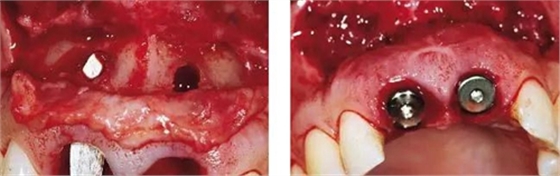

圖4、植入的種植體,初始穩(wěn)定性很好,由于骨缺損范圍大,選擇潛入式愈合。

圖5、種植體完全位于拔牙窩骨壁包圍的范圍內(nèi),距離唇側(cè)骨板至少2mm。

圖6、從磨牙后區(qū)用環(huán)形鉆獲取自體骨,并將其放置在種植體的表面。Geistlich Bio-Oss®骨顆?;旌涎悍胖迷谧泽w骨的外側(cè),防止自體骨的早期吸收。植骨可以穩(wěn)定軟組織外形。

圖7、植骨區(qū)外覆蓋Geistlich Bio-Gide®雙層膠原膜,使得植骨區(qū)更為穩(wěn)定。

圖8、從上腭獲取結(jié)締組織縫合在黏骨膜瓣上,進行軟組織增量。為了使得黏骨膜瓣充分減張情況下關(guān)閉,應(yīng)該使用瓣的分層技術(shù)。使用6-0或者5-0的可吸收線縫合關(guān)閉傷口。4個月后進行二期手術(shù)時通過分裂瓣技術(shù)將色素沉著的牙齦向冠方復(fù)位以恢復(fù)其原來的自然外形(在此沒有展示)。